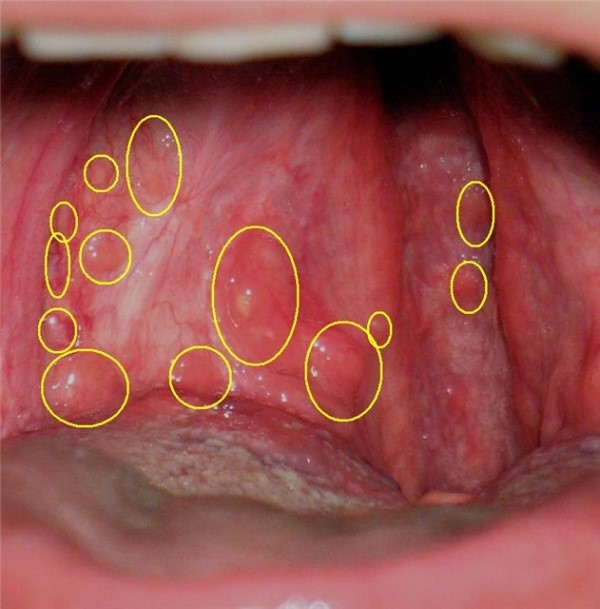

Фарингит

Является следствием перенесенного респираторного заболевания. Его симптомы, в том числе и волдыри на задней стенке горла, не исчезнут, пока не будет полностью излечена причина.

Волдыри в этом случае выглядят как небольшие пузырьки. наполненные прозрачной жидкостью. Они вызывают дискомфорт, но острой боли человек не испытывает .

Волдыри в горле: фото-материалы при фарингите